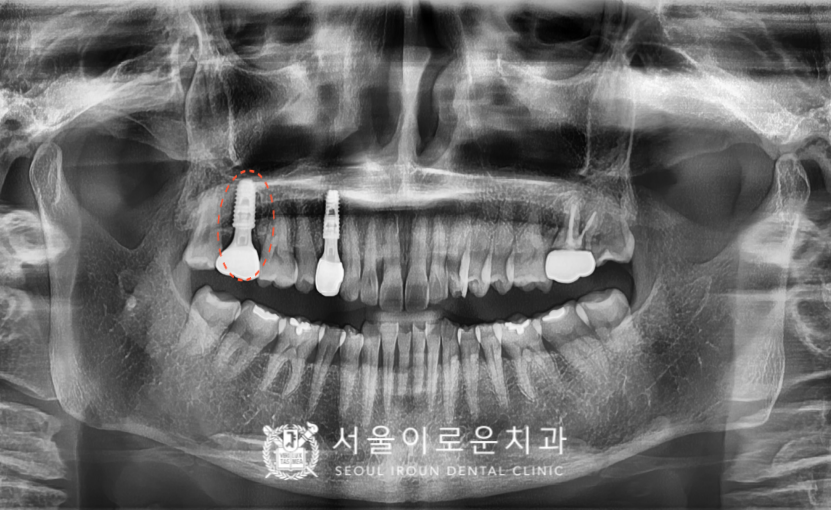

오른쪽 위 작은 어금니(#14) 부위의

임플란트 과정이 마무리되고 얼마 뒤

환.자분께서 첫 번째 큰 어금니 부위(#17)의

통.증을 호소하시며

다시 내원해 주셨는데요. (ㅠㅠ)

이전에 설명드렸던 대로

발치 후 임플란트를

진행하기로 계획하였습니다.

아무래도 염증이 심했던 부위라

발치 후 임플란트 즉시 식립은 어려워

염증을 깨끗하게 제거한 뒤

정기검진을 통해

발치 부위를 체크하였는데요.

주변 잇몸과 뼈가

잘 차오른 것을 확인한 뒤

발치 후 3달이 되는 시점에

뼈이식을 동반하여 임플란트를

식립해 드렸습니다.

임플란트 식립 후 2달 반 후에

osstell beacon이라는 장비를 이용하여

골유착 정도(isq)를 측정하여

안정 값을 확인한 뒤

보철물 과정을 진행하였습니다.

2개의 임플란트와 더불어

치경부 마모증 부위엔

레진치료를 모두 종결하였습니다!

✅ 전 > 후 ✅

(2024.02.22 ㅡ> 2024.08.02)